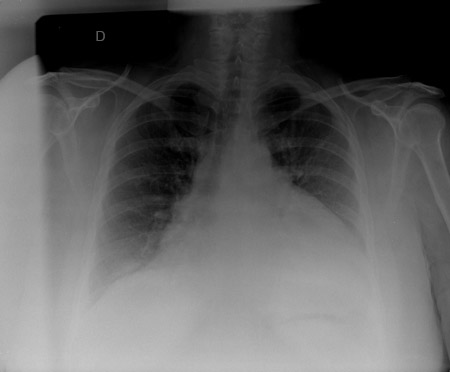

El RT en un paciente con un derrame pericárdico que muestra hallazgos típicos de una silueta cardíaca en forma botella de agua con una raya de grasa pericárdica gruesa y diferenciada.

De la colección del Dr. Rajdeep Khattar